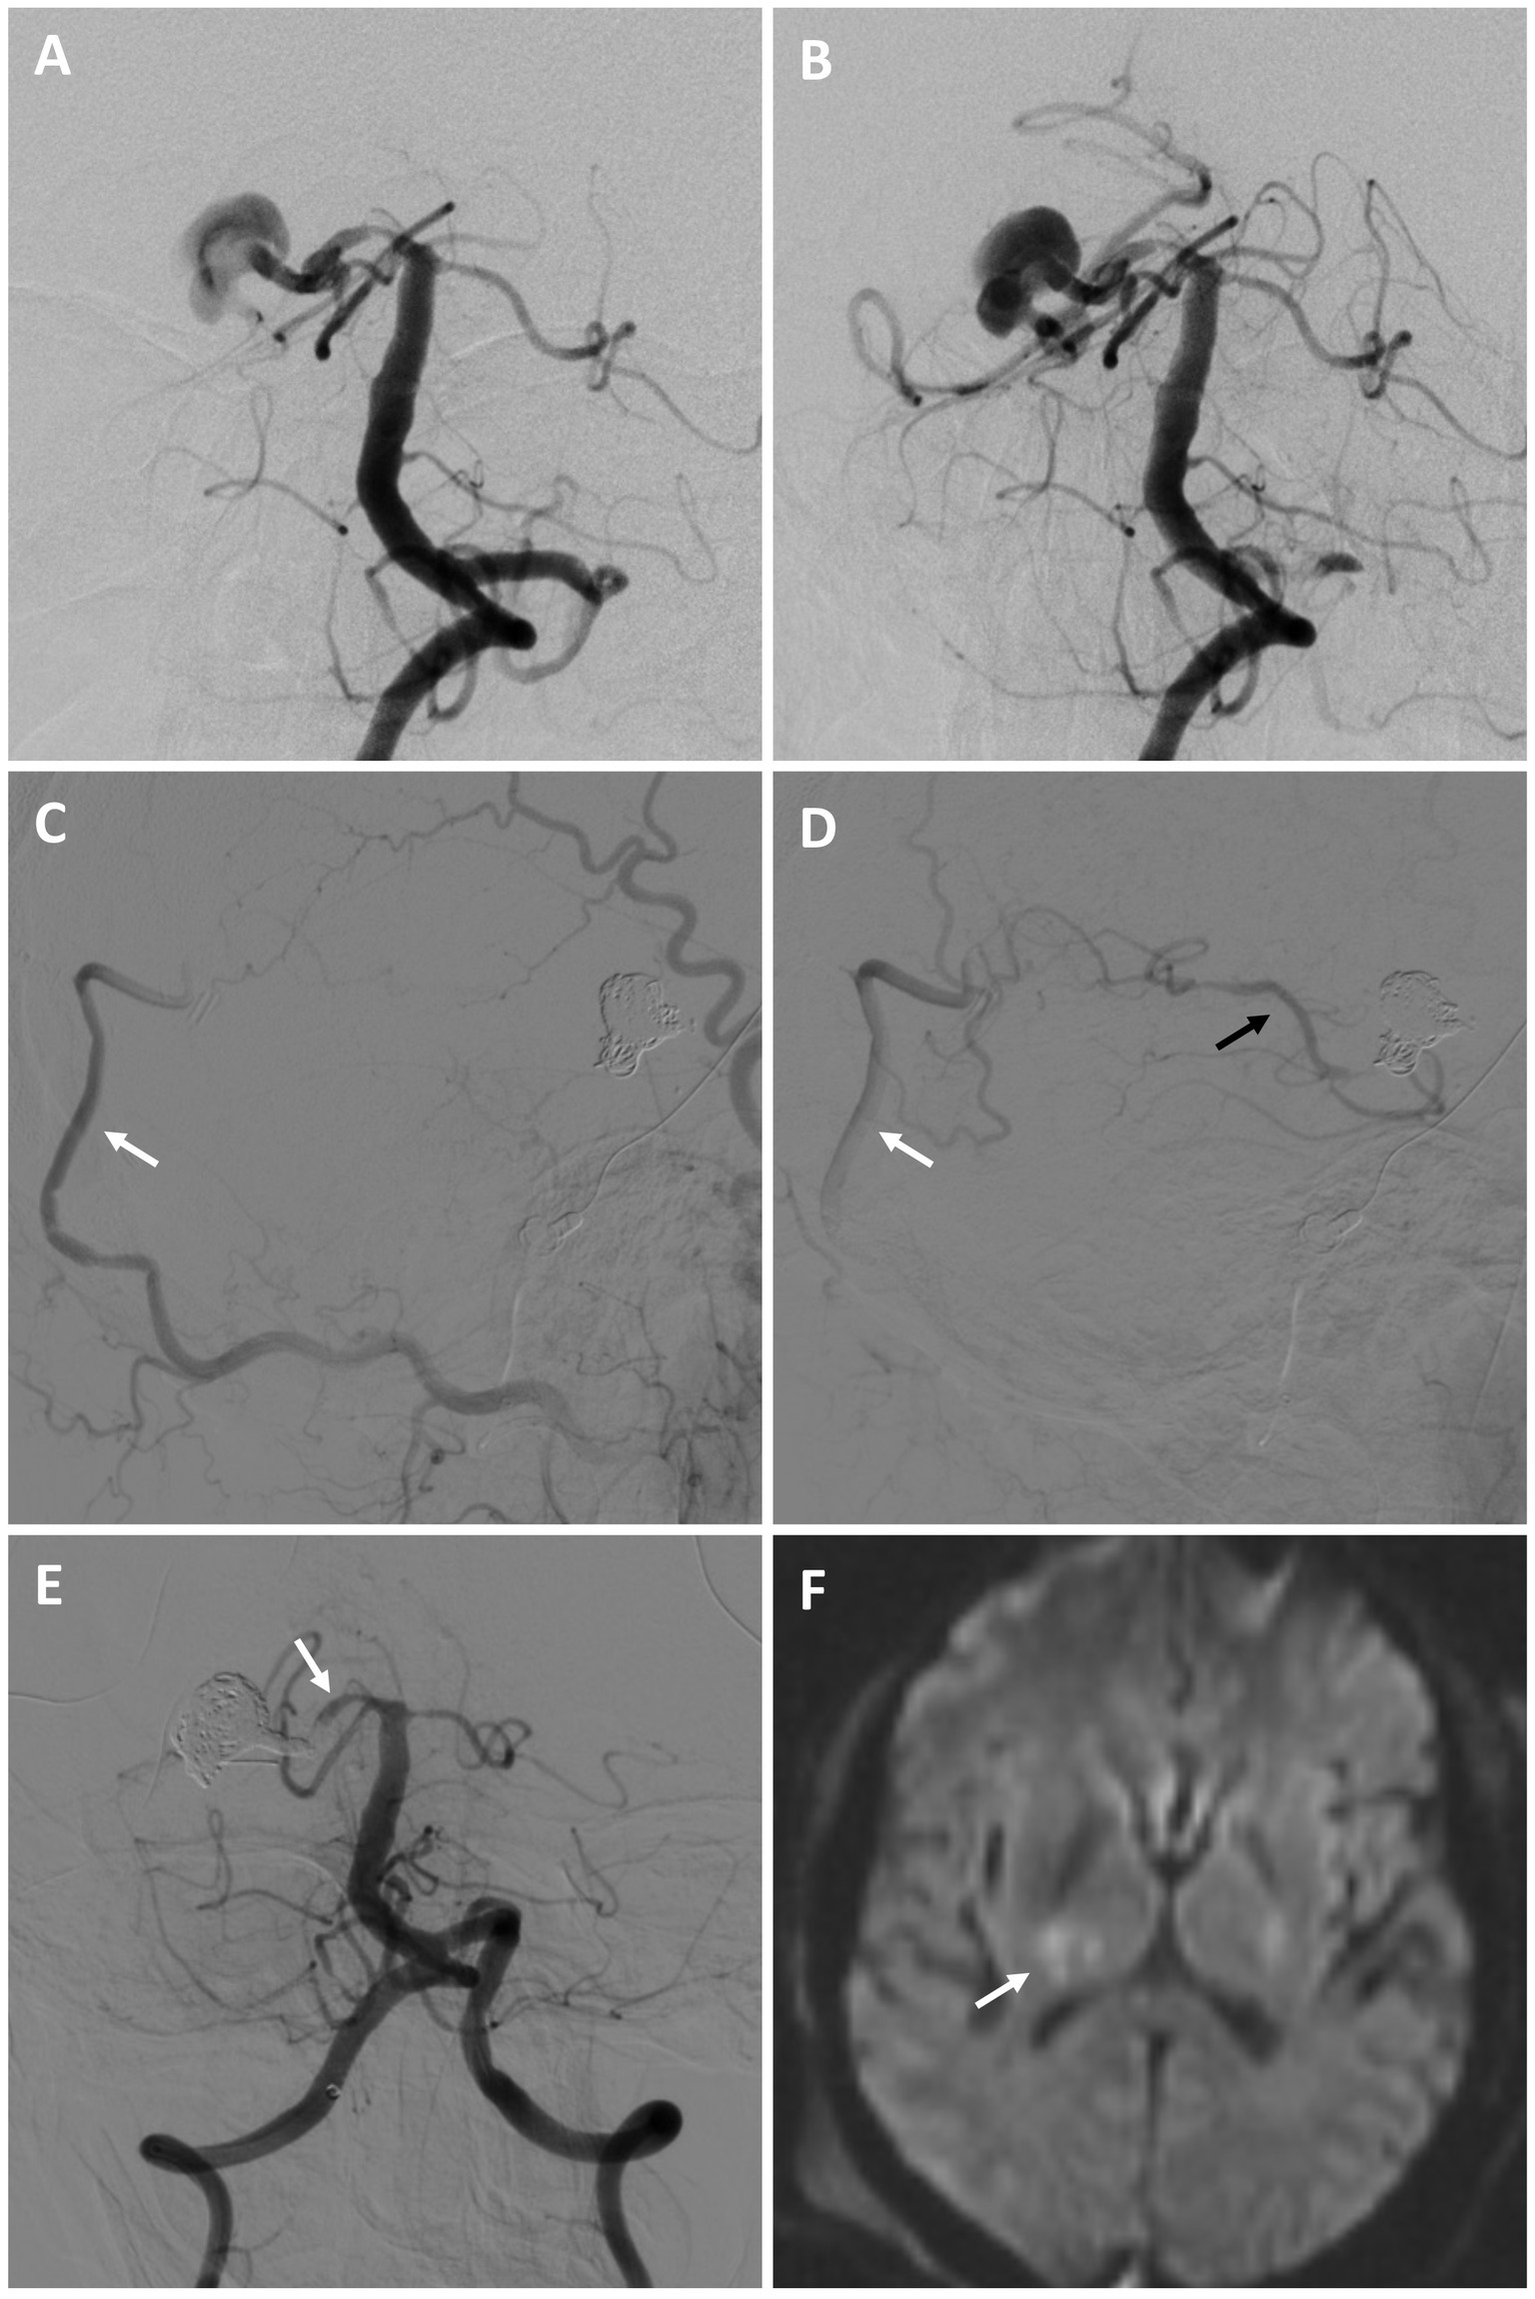

A 61-year-old male with a history of coil embolization of a ruptured (Hunt and Hess 1, Fisher 2), large, multilobed Acomm aneurysm arising from an unpaired left A1 presented 3 months later with SAH (Hunt and Hess 2, Fisher 3) and intraparenchymal hemorrhage, with aneurysm re-growth (Figures 3A–C). A repeat coil embolization was performed, leaving a neck residual to preserve the Acomm (Figure 3D). He was recommended for a right anterior cerebral artery (ACA) revascularization to allow aggressive Acomm aneurysm coiling and possible Acomm sacrifice given the rapid re-growth of the lesion. He underwent an A3-A3 bypass followed by aneurysm embolization with Acomm sacrifice 5 days later (as the aneurysm dome was already secure), allowing for filling of the right ACA through the bypass (Figures 3E,F). He had an uneventful post-operative course and was discharged home without focal neurologic deficits. On 3-month repeat angiogram the aneurysm had re-grown and the Acomm was patent (Figure 3G). A BTO was attempted to assess the bypass, however, the balloon was unable to be positioned. Flow diversion across the left A1-2 and repeat aneurysm coiling (including re-sacrifice of the Acomm) was performed (Figures 3H,I). After an uneventful recovery, he was discharged home neurologically intact. On 4-month follow-up angiogram there was no residual aneurysm, and the bypass was patent.

Figure 3

Patient #8. A 61-year-old male presented with SAH and intraparenchymal hemorrhage from a previously embolized Acomm aneurysm arising from an unpaired left A1 [(A) left ICA angiogram demonstrating initial Acomm aneurysm, and after coil embolization (B); (C) head CT demonstrating SAH and IPH]. A repeat coil embolization was performed, leaving a neck residual to preserve the Acomm [(D) post re-coiling angiogram demonstrating a neck residual and patent Acomm]. An A3-A3 bypass was performed, followed by repeat aneurysm embolization with Acomm sacrifice [(E,F) post-treatment angiogram demonstrating no residual aneurysm and filling of the right ACA through the bypass (highlighted by arrows)]. (G) 3-month repeat angiogram demonstrated aneurysm re-growth and an open Acomm, treated with flow diversion across the left A1-2 and repeat aneurysm coiling (including Acomm re-sacrifice) [(H,I) post-treatment angiogram demonstrating no residual aneurysm and filling of the right ACA through the bypass (highlighted by arrows)]. On follow up, the bypass was open and there was no aneurysm recurrence. The patient was neurologically intact and living independently.

Patient #10

A 53-year-old male with a history of chronic kidney disease was referred for a large right fusiform P2 aneurysm with a proximal dysplastic P1 vessel (Figures 4A,B) after an unsuccessful attempt at flow diversion at an outside facility. He was neurologically intact. He was recommended for a combined open revascularization and endovascular internal embolization on multidisciplinary review, with a plan to keep the proximal P1 open, despite its dysplastic appearance, to preserve perforator flow. He underwent an uneventful right OA to P4 bypass with a DLCFA interposition graft. The same day he underwent a right P1 BTO that confirmed bypass patency and did not result in neurologic changes. This was followed by a coil embolization/vessel sacrifice of the right P2 aneurysm (Figures 4C–E). Flow into the proximal right P1 was preserved. He experienced a small right thalamic stroke following aneurysm sacrifice (Figure 4F), likely from perforators off the severely diseased and sacrificed P2 segment, as well as a small right occipital stroke. This resulted in mild left hemiparesis and a partial left hemianopsia that required a short inpatient rehabilitation stay. On 9-month follow up he was living at home and performing all activities of daily living independently.

Figure 4

Patient #10. A 53-year-old male was referred for a large right fusiform P2 aneurysm with a proximal dysplastic P1 vessel [(A,B) AP angiogram of the left vertebral artery]. A prior attempt at flow diversion was aborted due to unfavorable anatomy. He underwent a right OA to P4 bypass with a DLCFA interposition graft, followed by a coil embolization/vessel sacrifice of the right P2 aneurysm (keeping the proximal right P1 patent) after BTO [(C,D) serial lateral images from a right external carotid artery injection demonstrating patency of the bypass (white arrows) and backfilling of the PCA territory (black arrow)]. The right P1 was kept open to preserve perforator flow [(E) AP angiogram of the right vertebral artery (arrow highlights right P1)]. Post-operatively he experienced a small right thalamic stroke [(F) axial diffusion-weighted MRI, arrow highlighting stroke], likely from perforators off the severely diseased and sacrificed P2 segment, as well as a small right occipital stroke of unclear etiology (not shown). He had left mild hemiparesis and a partial left hemianopsia. This significantly improved on 9-month follow, where he was living at home and performing all activities of daily living independently.